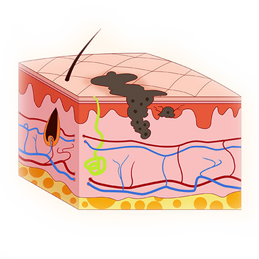

ΤΛΖτΑ© «“Μ÷÷≥ΘΦϊΒΡΕώ–‘÷ΉΝωΘ§”…ΤΛΖτœΗΑϊ“λ≥Θ‘ω…ζΥυ“ΐΤπΘ§÷ς“ΣΖ÷ΈΣ»ΐ÷÷άύ–ΆΘΚΜυΒΉœΗΑϊΑ©Θ®BCCΘ©ΓΔΝέΉ¥œΗΑϊΑ©Θ®SCCΘ©ΚΆΚΎ…ΪΥΊΝωΘ®MelanomaΘ©ΓΘΝΥΫβΤδ≤Γ“ρΓΔ‘γΤΎ÷ΔΉ¥ΦΑΖά÷ΈΖΫΖ®Θ§”–÷ζ”ΎΗϋΚΟΒΊ±ΘΜΛΤΛΖτΫΓΩΒΓΘ

ΚΎ…ΪΥΊΝωΘ®MelanomaΘ© «“Μ÷÷‘¥”ΎΤΛΖτ÷–ΚΎ…ΪΥΊœΗΑϊΒΡΑ©÷ΔΓΘΚΎ…ΪΥΊœΗΑϊΗΚ‘π≤ζ…ζΚΎ…ΪΥΊΘ§’β÷÷Έο÷ ΈΣΤΛΖτΓΔΆΖΖΔΚΆ―έΨΠΧαΙ©―’…ΪΓΘΨΓΙήΚΎ…ΪΥΊΝωΉν≥ΘΦϊ”ΎΤΛΖτΘ§ΒΪΥϋ“≤Ω…“‘‘Ύ―έΨΠΓΔΩΎ«ΜΓΔ≥ΠΒά…θ÷ΝΤδΥϊ≤ΩΈΜ≥ωœ÷ΓΘ